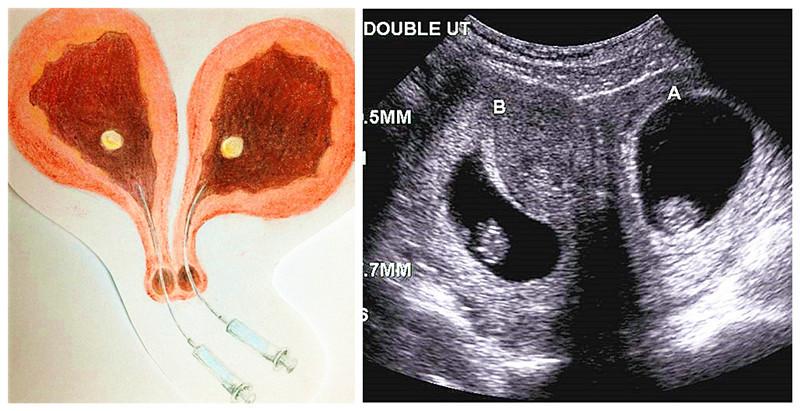

【台灣醒報記者李昀澔台北報導】真是罕見!1位「雙陰道、雙子宮」的35歲女性,最近透過試管嬰兒技術,喜獲雙胞胎姐妹花。台北榮總團隊18日發表國內首例經由試管嬰兒技術,讓雙子宮女性2側子宮都順利懷孕的特殊案例。

北榮婦女部不孕症科主任李新揚指出,雙陰道雙子宮發生率約3千分之1,醫學文獻共計載10餘例雙陰道雙子宮女性自然懷孕案例,但多為單子宮懷單胞胎,藉由試管嬰兒技術懷上「一邊一胎」,目前全球應無先例。

李小姐嘗試懷孕多年未果,原已打算放棄,但李新揚告訴她,「雙陰道雙子宮絕對不是不孕的主因」,讓她決心重啟試管嬰兒療程。李新揚解釋,只要精卵及子宮、輸卵管功能都正常,雙陰道雙子宮女性仍能自然懷孕,而雙陰道女性的陰道常呈一邊寬、一邊窄,李小姐過去接收的試管嬰兒手術,都是由陰道較寬、較方便醫師操作的右側植入胚胎,李新揚認為,左側子宮順利懷孕的機率說不定較高,因此決定2側都植入胚胎。

檢查也發現,李小姐的胚胎品質無虞,應是不易著床才導致多年不孕。李新揚採用北榮團隊曾發表於美國生殖學會的「子宮內膜輕刮術」,以提高胚胎著床機會。李新揚分析,該技術是以金屬刮勺輕刮子宮內膜,製造多個細小傷口,為修補傷口,骨髓幹細胞會移動至子宮內膜,分泌多種生長因子以促進傷口癒合,而生長因子同時也能強化胚胎著床的能力。完成子宮內膜輕刮術後,再將胚胎分別植入李小姐2個子宮。